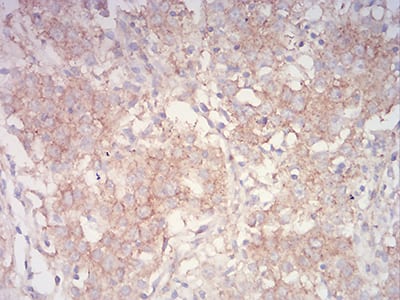

Immunohistochemical analysis of paraffin-embedded human stomach cancer tissues using PYCARD mouse mAb with DAB staining.